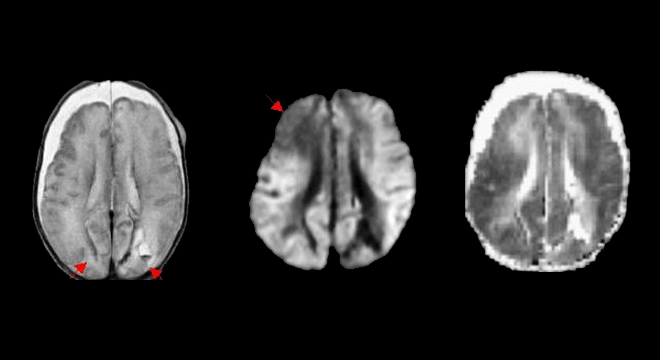

Schütteltrauma beim Kind: Computertomographie des Schädels

• Computertomographie: damit können Blutungen unter der Schädeldecke sowie Hirnverletzungen sichtbar gemacht werden.

• Magnetresonanztomographie : Blutungen im Gehirn werden sichtbar (sogenannte shearing injuries)